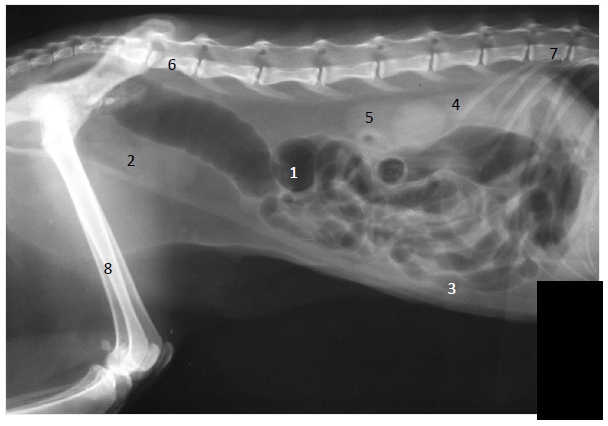

Considere na imagem radiográfica abaixo (radiografia laterolateral do abdome de um doméstico) as estruturas anatômicas numeradas de 1 a 8.

Assinale a alternativa que apresenta corretamente a denominação dessas estruturas.